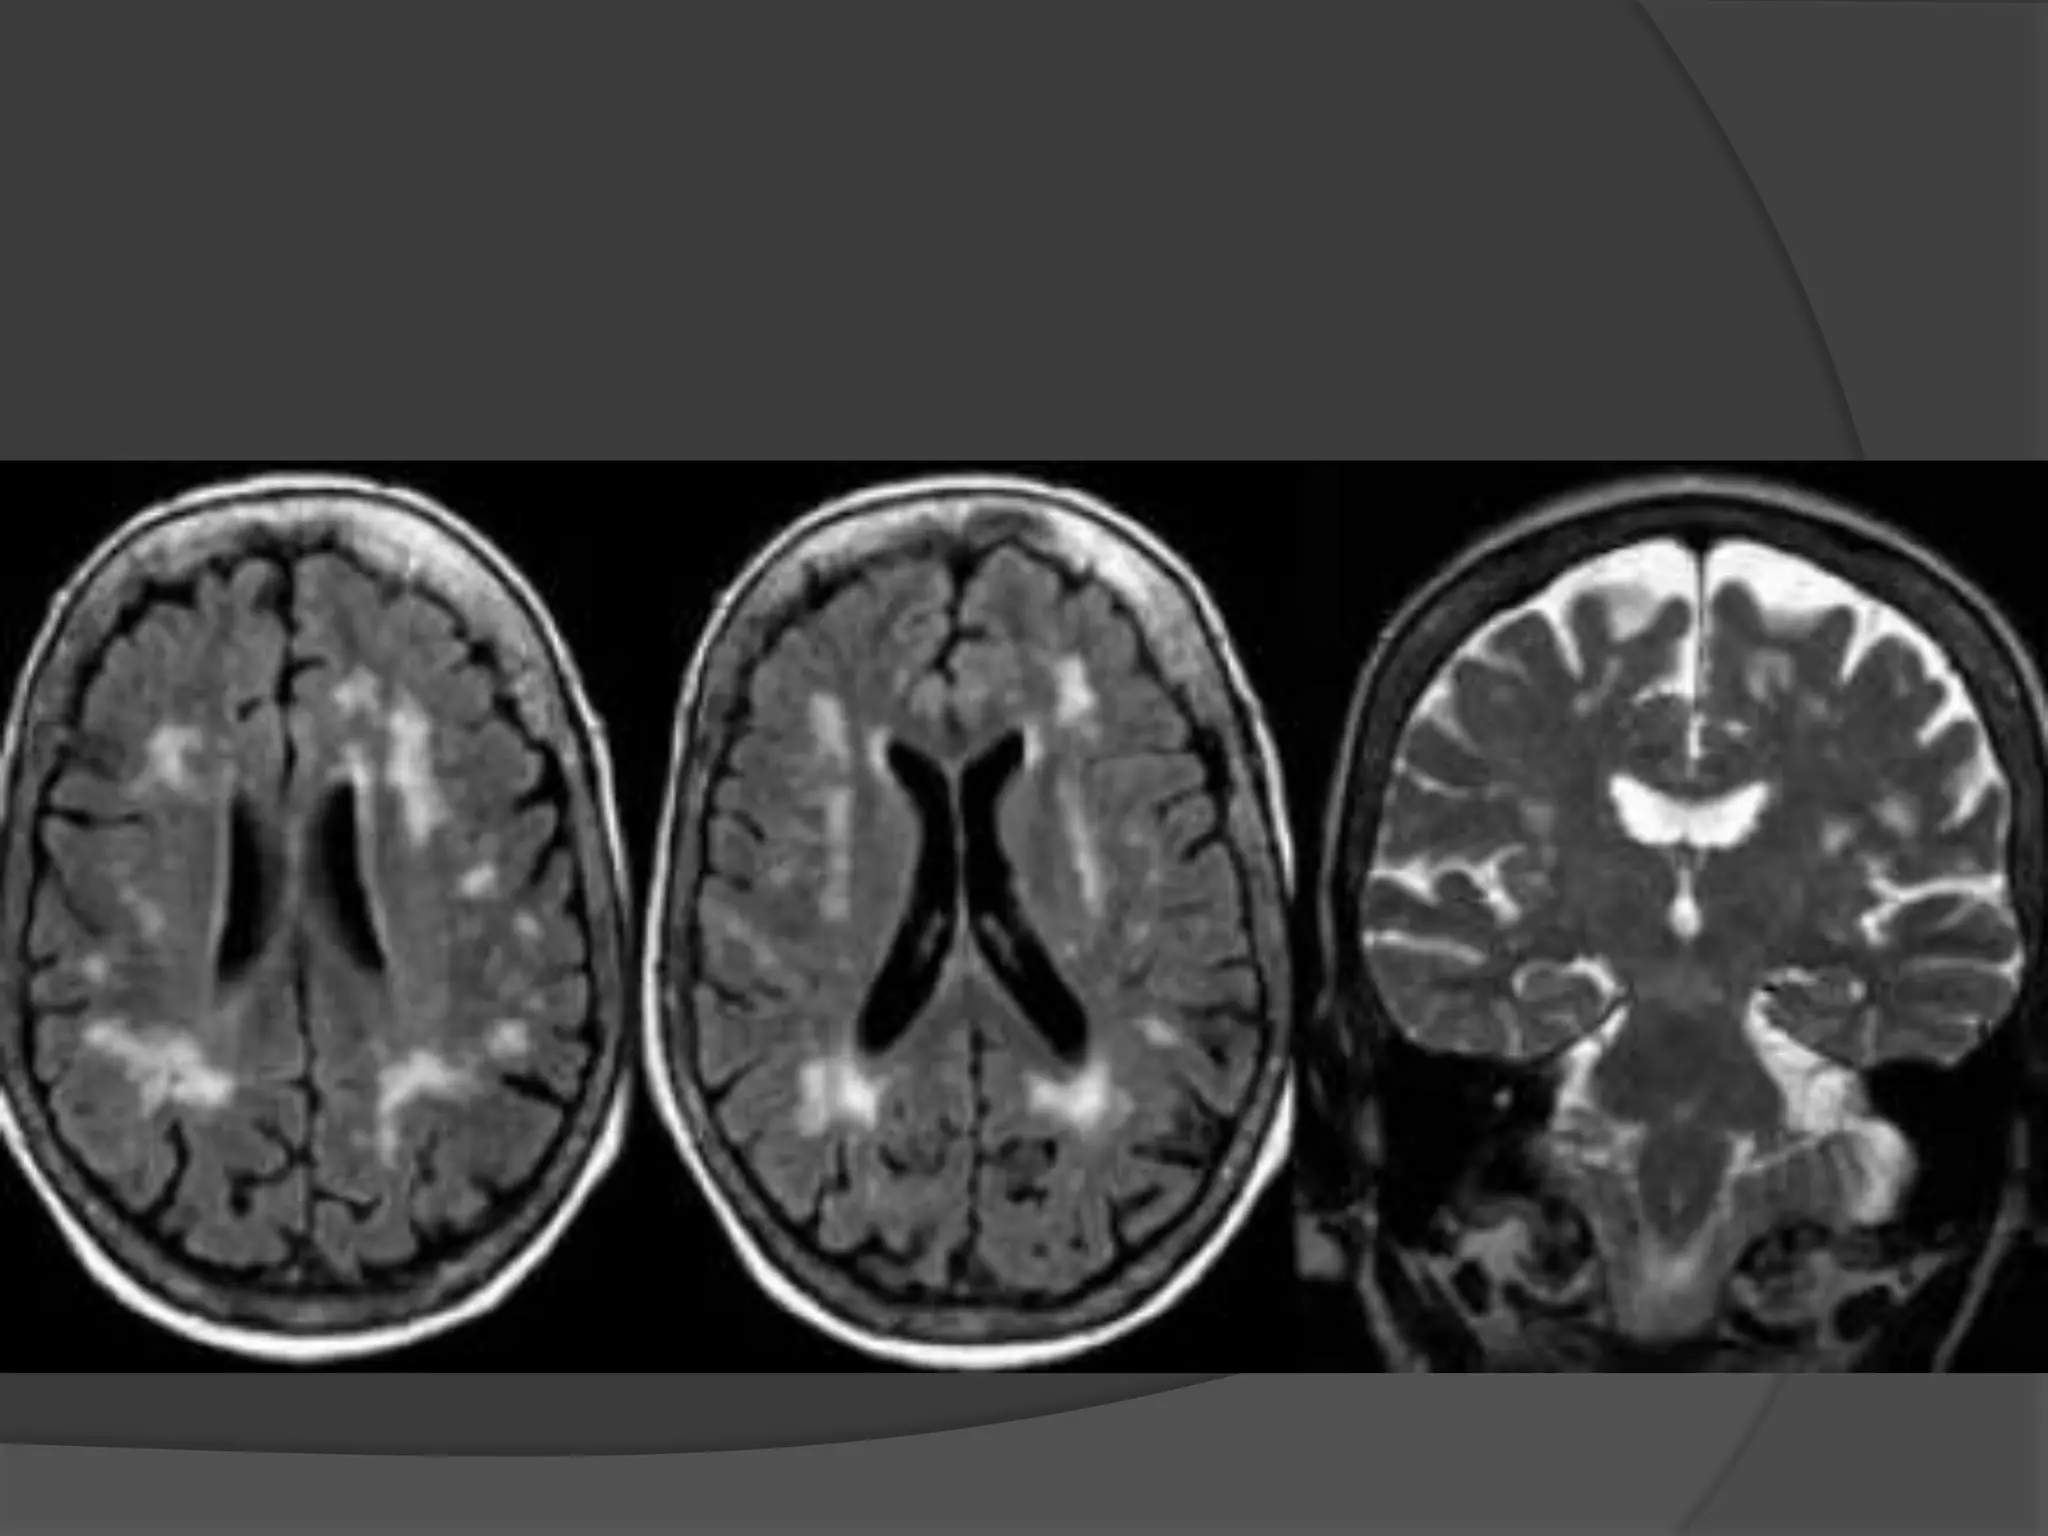

Fluid Attenuated Inversion Recovery

Special type of MRI scan



T1 image is inverted & added to

the T2 image

Contrast between grey & white

matter is doubled & the normal

CSF signal is suppressed.

Special indications

1.

To detect Sclerosis of

hippocampus in Temporal lobe

epilepsy.

2.

To Localize the areas of

abnormal metabolism in

degenerative neurological

diseases.

NORMAL PRESSURE

HYDROCEPHALUS

MRI findings include

Ventricular enlargement out of proportion to sulcal

atrophy.

Prominent periventricular hyperintensity (halo).

Prominent flow void in the aqueduct and third

ventricle, the so-called jet sign, (presents as a dark

aqueduct and third ventricle on a T2-weighted image

where remainder of CSF is bright)

Thinning and elevation of corpus callosum on sagittal

images